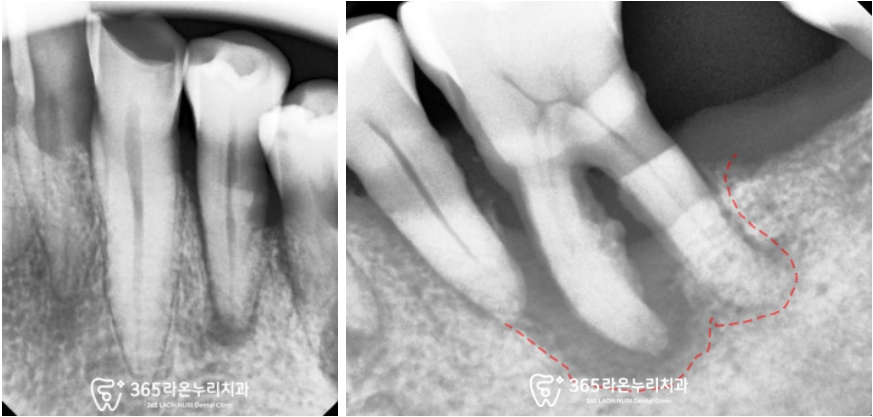

치주 질환으로 인하여

잇몸이 퇴축되고 낮아짐과 동시에

치아의 뿌리 부근이 드러나면서

경계부가 패이고 약해져있습니다.

또한 그 틈으로

치은연하치석까지 쌓여있는 것이

보이네요.

생각보다 치근 끝에 염증이 크고

치조골 소실도 존재하여

뼈이식도 함께 동반했습니다.